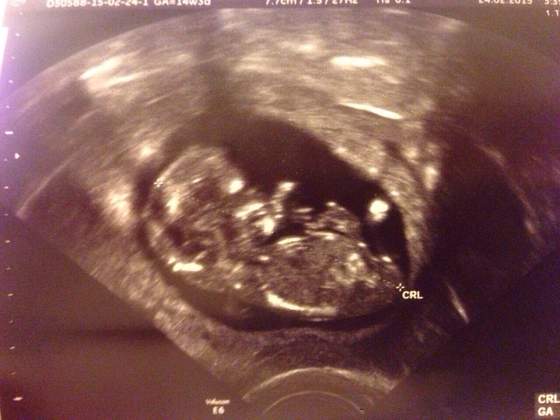

U nas z dzidzią wszystko dobrze, rozwija się ok. Wymiarów ani szczegółów nie znam bolekarz nic nie mówił.. dobrze, że w piątek wizyta u mojego gina to się wszystkiego szczegółowo dowiem. Najważniejsze, że wszystko jest dobrze:-)

Sysiq <3 cudowny! Idealny!

Sysiq gratuluję Wiktorka:-) Cudny synuś i jaki juz duży. Który to tydzień????